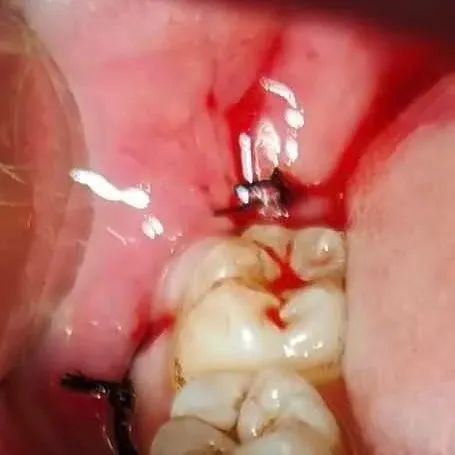

是的,有可能。智齿炎症可诱发肾病患者免疫异常激活,攻击肾脏组织,导致红细胞、尿蛋白的加重,一些患者也会出现血肌酐的异常升高。这种情况,需要及时找牙科医生进行抗炎处理,该使用抗生素可以用抗生素,牙科常用的比如头孢类(如头孢呋辛)、硝唑类(如甲硝唑)这些药物,肾友是可以按需使用的,肾毒性小。在抗炎处理,肾友的炎症反应彻底恢复后,通常尿检、血肌酐异常波动的情况可以恢复到原来水平,需要复查。对于经常牙齿发炎的患者而言,不要觉得就是上火,吃药对付过去就行了,应该找牙科看看坏牙,该怎么治怎么治,该拔除可以拔除。一些患者可能担心拔牙也算是个小手术,会有创伤,对肾不好。其实,这就是一个长痛短痛的问题,不拔的话,智齿经常发炎就对肾好了吗?反反复复的炎症,搞得肾病就没消停过,指标怎么容易好呢?...